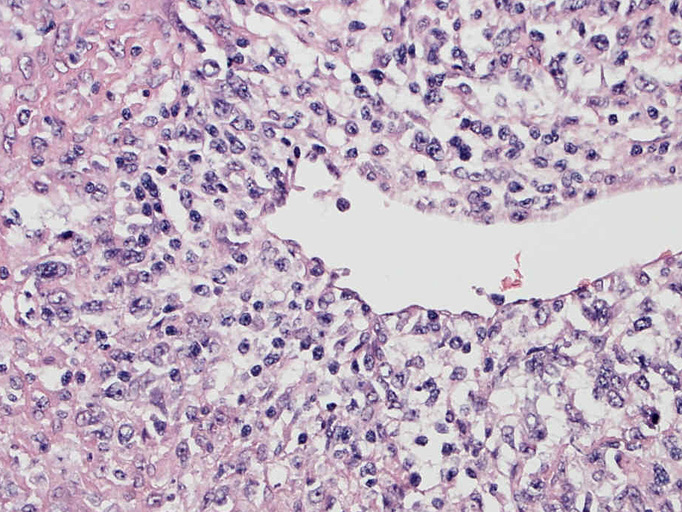

EBUS-GS(ガイドシース併用気管支腔内超音波断層法)による肺生検組織病理所見.

血管周囲性に大型類円形核や不整形核をもつ腫瘍細胞がシート状密に浸潤増殖している. Mitosisが多く認められる.細血管閉塞や破壊の所見がある.

間質にもシート状の腫瘍細胞浸潤がある. 大小 pleomorphicな傾向.(A, B). necrosisが認められる(C). 細気管支上皮直下まで密な浸潤あり, 小型リンパ球が混在している.(D)

血管中心性浸潤. 障害された血管内に血栓が形成されている.CD20陽性細胞がシート状密に浸潤, CD3陽性T細胞が多く混在している. EBER-ISH陽性 EBV感染細胞が多数認められ, >50 hpf, 定義より Grade3となる. 陽性細胞のサイズは大小さまざまであることに注意. Lymphomatoid granulomatosisの病態(WHO5thの診断では EBV-positive diffuse large B-cell lymphomaになる)をとっているが MTX-associated LPDの一型とするべき症例かもしれません.